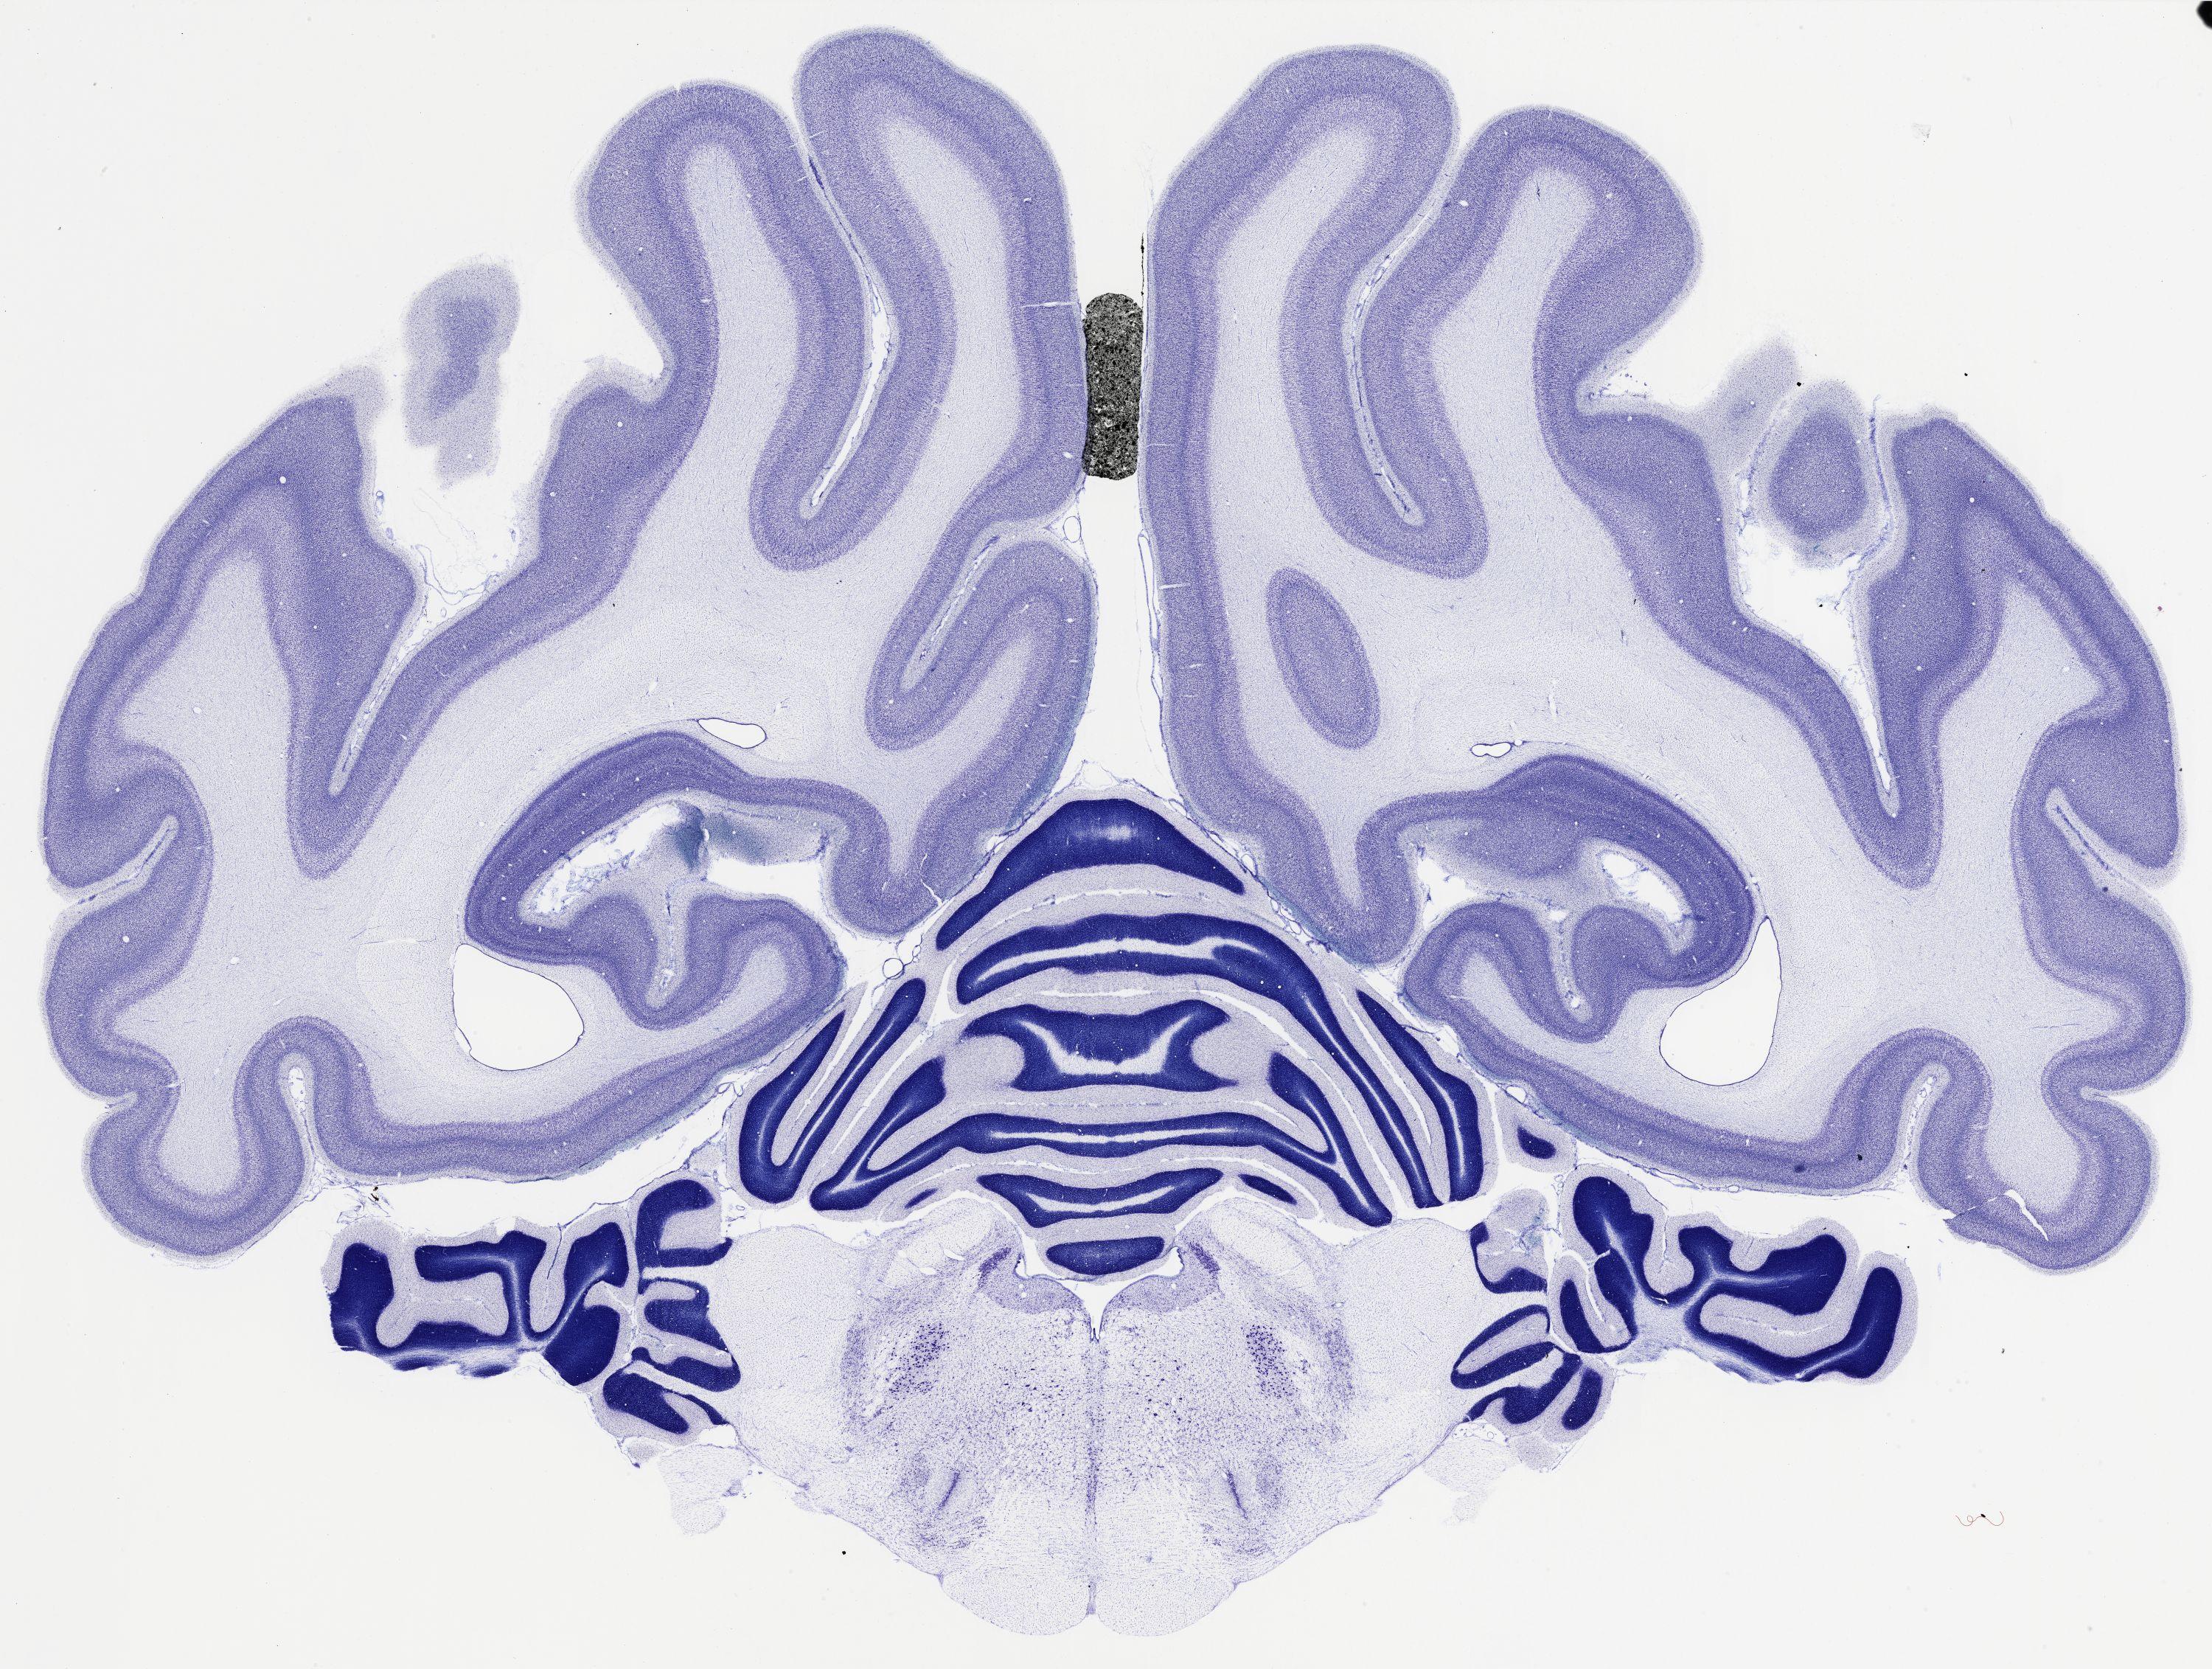

Datasets -> Chlorocebus Aethiops -> Nissl, coronal, histo, Whole-Brain, adult

[ Metadata ]   ·   Source: NeuroScience Associates

thumbnail

524